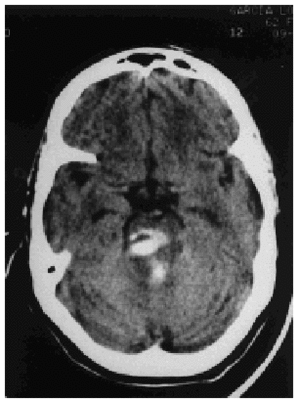

Paciente mujer de 62 años de edad, con antecedentes de hipertensión arterial, que presenta súbitamente deterioro neurológico e ingresa en urgencias de nuestro hospital en coma profundo con una puntuación de Glasgow de 5 y cifras de hipertensión arterial de 200/100 mmHg. En la exploración destaca miosis no reactiva, reflejos corneales y movimientos oculocefálicos ausentes. Previa sedorrelajación se procede a intubación orotraqueal y conexión a ventilación mecánica, y se realiza una tomografía computarizada helicoidal craneal (fig. 1) que objetiva hemorragia mesencefálica y protuberancial abierta a cuarto ventrículo. El electrocardiograma presenta discreta lesión subepicárdica en cara inferior < 1 mm y más acusada en cara lateral baja con cambios recíprocos en I y aVL (fig. 2). Analíticamente sólo destaca leucocitosis de 24.000 mm3 y curva típica de creatinfosfocinasa, fracción MB y troponina T con un pico máximo de 1.503, 152 y 2,90 UI/l, respectivamente. Se realiza traqueostomía percutánea siendo dada de alta en la misma situación neurológica a los 10 días. Diagnóstico: infarto agudo de miocardio secundario a hemorragia mesencefálica y protuberancial.

Figura 1.